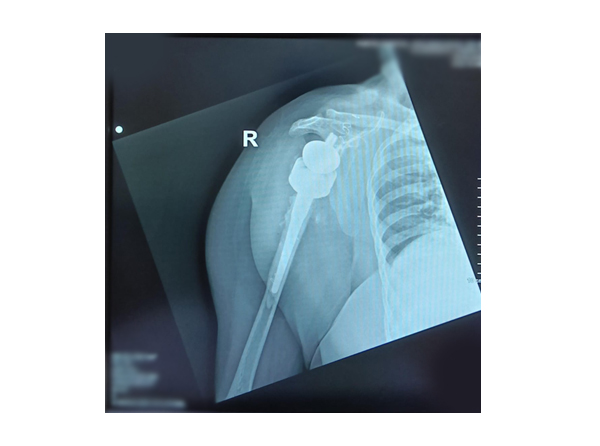

Shoulder Replacement Surgery

Shoulder replacement surgery is a procedure to relieve pain and restor